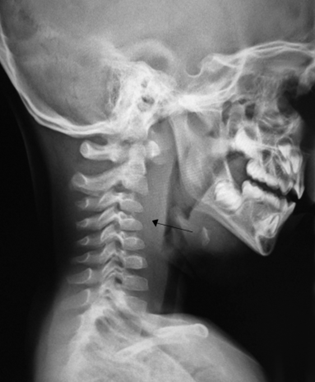

Lateral neck radiographs typically demonstrate a widened retropharyngeal or prevertebral space. (See Figure 3.) The film should be taken in the lateral plane during patient inspiration with the neck in extension. Failure to follow proper technique can lead to false-positive studies. In children younger than 4 years of age, the retropharyngeal space at the level of C2 should be less than half the width of the vertebral body at that level. An abnormally wide space is considered when the diameter of the space is greater than the size of the vertebral body at C2, or a gradient of 7 mm at C2 or 14 mm at C6.18 (See Figure 4.)

Figure 3. Retropharyngeal Abscess |

Lateral X-ray demonstrating retropharyngeal abscess (black arrow). Note the increased prevertebral space (7 mm at C2). Courtesy of James Heilman, MD. Retroabscess10.JPG. https://commons.wikimedia.org/wiki/File:Retroabscess10.JPG CC BY-SA 3.0 |